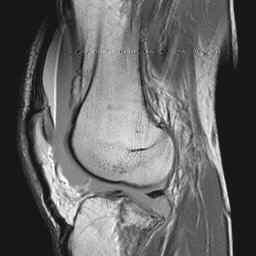

CASE 1: These three MRI images are from the 50 year old male who fell 1 day prior to presentation and whose radiographs are displayed on the KNEE RADIOGRAPHY page.

Image 1: Sagittal gradient echo image demonstrates four distinct bands of signal in the knee joint effusion. CLICK TO ENLARGE.